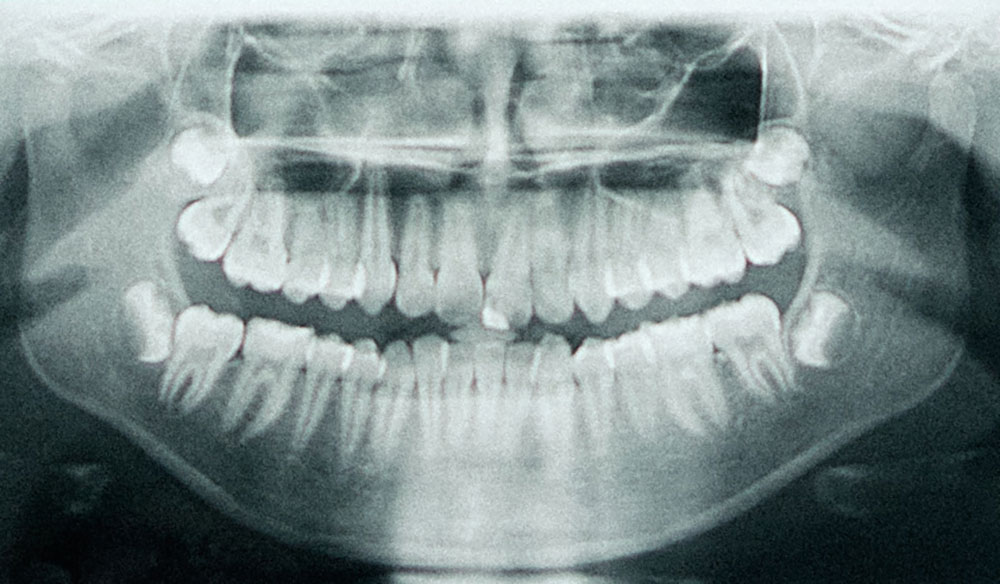

Röntgendiagnostik – präzise und verantwortungsvoll

Um Erkrankungen im Inneren des Zahns oder Kieferknochens sicher zu erkennen, ist die radiologische Diagnostik ein unverzichtbarer Bestandteil. Da viele Patient:innen gegenüber Röntgenstrahlung sensibel sind, wird in der Praxis nach dem ALARA-Prinzip gearbeitet – as low as reasonably achievable.

Das bedeutet: Die Aufnahme erfolgt mit der geringstmöglichen Strahlendosis bei gleichzeitig bester Abbildungsqualität. Zudem werden Strahlenschutzmaßnahmen wie Röntgenschürze, Schild, Einblendung und modernste Röntgengeräte verwendet. Vor jeder Röntgendiagnostik besprechen wir die Thematik mit Ihnen und wägen die Vor- und Nachteile ab, ob eine Aufnahme zwingend erforderlich ist.

Eine Wurzelkanalbehandlung beschreibt eine Erkrankung aus dem Zahninneren. In der Mitte des Zahnes befindet sich quasi das „Herz“ des Zahnes während der Zahnentwicklung, die sogenannte Pulpa. Der vollausgebildete Zahn kann jedoch ohne die Pulpa „überleben“, da er über das Knochengewebe versorgt wird. Wenn die Pulpa entzündet oder abgestorben ist, besiedeln Bakterien die Hohlräume und können zu einer Entzündung an der Wurzelspitze führen, die im Röntgenbild sichtbar ist.

Im Rahmen einer Wurzelkanalbehandlung werden die Hohlräume im Zahninneren von den Bakterien gesäubert, damit sich der Körper selbst heilen kann. Die Behandlung erfolgt in 2-3 Sitzungen. Abschließend wird der Hohlraum gefüllt und der Behandlungserfolg mit einer radiologischen Kontrolle in derselben Sitzung überprüft.